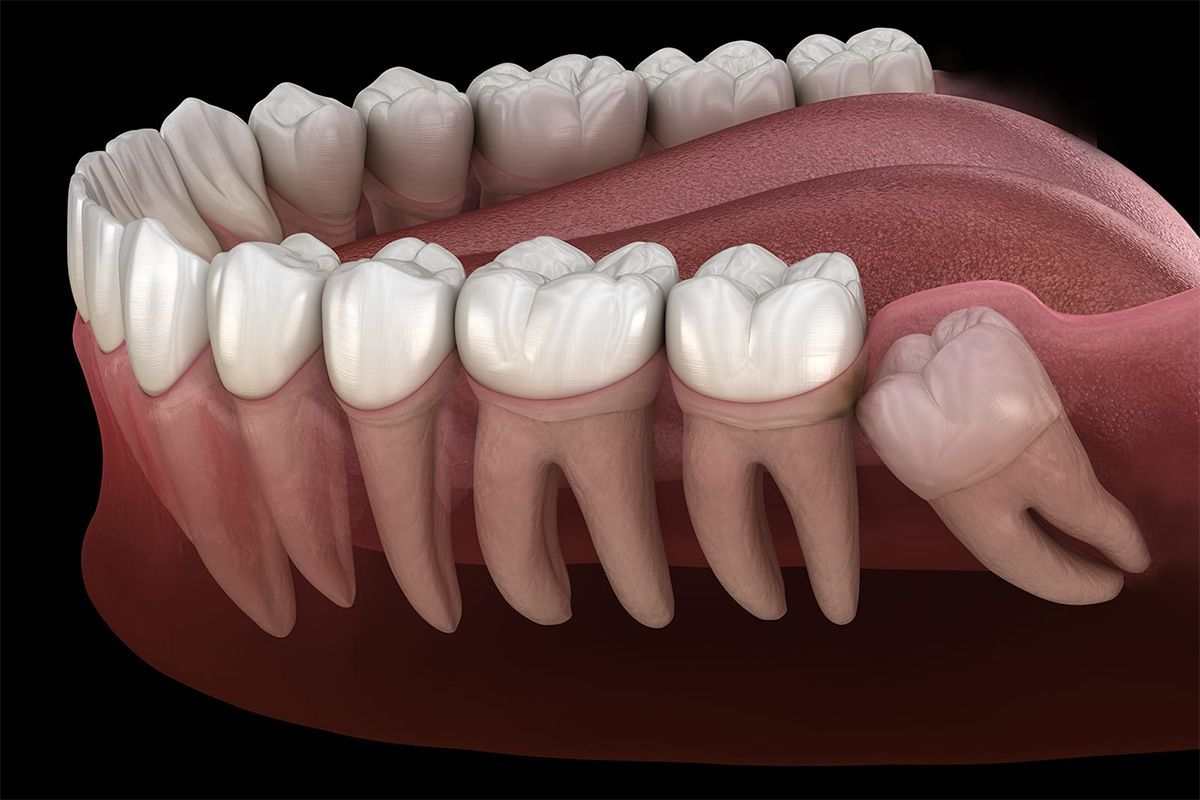

20 Yaş Diş Çekimi

20 yaş dişi; genelde 16-25 yaş aralığında çenenin iki tarafının sonunda olmak üzere toplamda 4 adet çıkan üçüncü büyük azı...

Devamını Oku

Gömülü Diş...

Gömülü dişler, ağız cerrahisinde en sık görülen olgulardır. Ağızda sıklıkla alt-üst 20 yaş dişleri, üst çene köpek dişleri ve...

Cerrahi Tedaviler

Ağız, Diş ve Çene Cerrahisinde yapılan tedaviler daha çok gömük yirmi yaş çekimi olarak düşünülmektedir.